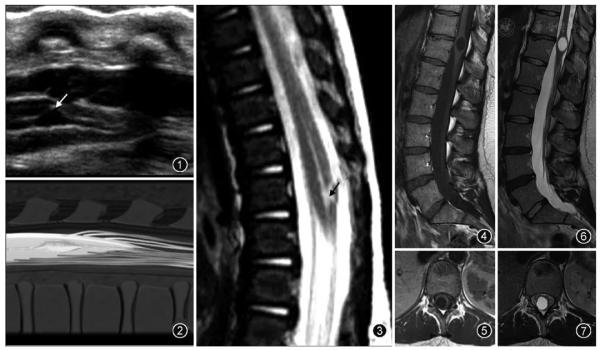

第五腦室,也稱終室(ventriculus terminalis, VT),是位於脊髓圓錐內、由正常室管膜組織包繞且內含腦脊液的囊性腔室。該腔室結構由Stilling在1859年首次描述為與蛛網膜下腔相通且擴張的脊髓中央管,但Krause不認同Stilling提出的該腔室與蛛網膜下腔相通的觀點,並於1875年在觀察到這個囊腔的壁是由正常室管膜細胞構成後提出了"第五腦室"這一概念。

在兒童時期,無臨床症狀的第五腦室被認為是一種正常的發育現象,無需進行干預,但是也有部分具有第五腦室的兒童,合併一些先天畸形,例如脊髓栓系綜合徵、脊髓脊膜膨出、腰骶部脂肪瘤等。成人的第五腦室可以沒有任何臨床症狀,但當脊髓圓錐受到第五腦室壓迫時,可產生括約肌功能障礙,運動和感覺功能異常,坐骨神經痛等症狀。

第五腦室屬於良性改變,預後比較好,囊腔可在隨訪的數年中沒有明顯變化,術後病灶殘留也可以長期保持穩定狀態,第五腦室的體積與臨床症狀程度並沒有正比關係,但第五腦室大小與術後的療效有關,直徑越大的囊腔療效越差。

超聲是診斷胎兒或新生兒第五腦室的一種常用檢查方法。第五腦室在超聲矢狀切面圖上顯示為脊髓圓錐區域囊狀擴張的低迴聲區並可與中央管相通,在超聲橫斷切面圖上表現為擴張的低迴聲囊腔且與周圍脊髓組織有著較為清楚的分界。

MR檢查為診斷第五腦室的主要手段。第五腦室在MRI上通常表現為脊髓圓錐內邊緣清楚的卵圓形囊腔,形態規則,囊壁光整,且與周圍正常的脊髓組織分界清楚,囊內為T1WI低、T2WI高的腦脊液訊號,囊內分隔及囊周水腫性改變比較少見,增強掃描後囊壁不強化。第五腦室需要與位於脊髓圓錐的囊性腫瘤如室管膜瘤、星形細胞瘤以及膿腫相鑑別,囊性腫瘤和膿腫的囊壁通常有不同程度的強化。脊髓圓錐的轉移瘤很少見,MRI表現通常為腫瘤強化且周圍伴有明顯水腫。脊髓背側的嚴重損傷也可發展為囊性病灶,但目前報道的大多數第五腦室病例並無外傷病史。脊髓內的表皮樣囊腫和皮樣囊腫由於成分複雜導致MRI表現多變,而第五腦室的MRI表現單一。